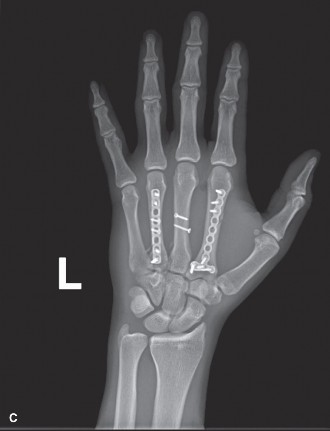

You notice that one of his fractures has been fixed with only interfragmentary screws while the other fractures have been fixed with plates and screws (Fig. 4–1C).

Figure 4–1 C

Basic requirements for fixation of a tubular bone shaft fracture in the hand using only interfragmentary screws include which of the following?